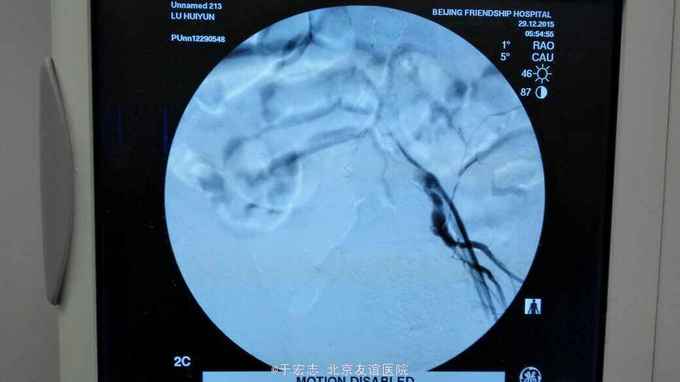

男性76岁,腹主动脉骑跨栓塞,经外院ct证实,病程3天,转至我院。

全腔内技术操作,用8F rotarex机械取栓导管操作,术前留置股静脉鞘,边操作边放静脉血,减少毒素吸收。静脉血经自体血回收处理。 操作完成后以血管缝合器缝合股动脉穿刺点,加压包扎。 患者转重症医学科途中出现心跳骤停,于手术室心外按压2小时复苏成功,转重症医学科血滤治疗。术后五小时生命体征均可维持,但家属还是放弃进一步治疗转运回当地治疗。